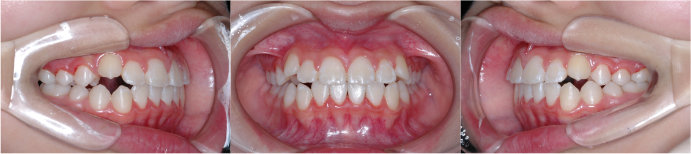

| <治療後> |

|

| 主訴 |

上の前歯が出ている |

| 診断名 |

上顎前突 |

| 年齢 |

8歳 |

| 使用装置 |

マルチブラケット装置/ヘッドギア |

| 抜歯部位 |

永久歯の抜歯は無し |

| 治療期間 |

3年6か月 |

| 治療費概算 |

検査・診断料:5万円+税 装置・技術料:25万円+税 来院ごとの処置・管理料:5,000円+税 保定装置料:5万円+税 |

| リスク・副作用 |

特になし |